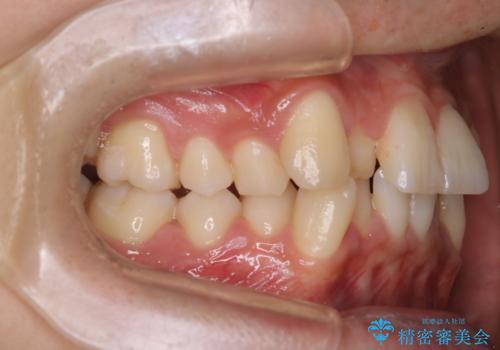

- 凸凹を治したいと来院された患者様です。

インビザラインにて、遠心移動を行いながら綺麗に配列することができました。

側切歯が低位の場合、反対咬合を改善した後に挺出させるのはワイヤーの方が適しています。